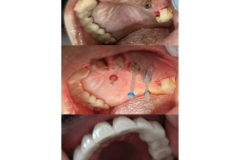

If you are self-conscious because you have missing teeth, wear dentures that are uncomfortable or don’t want to have good tooth structure removed to make a bridge, talk to your dentist to see if dental implants are an option for you.